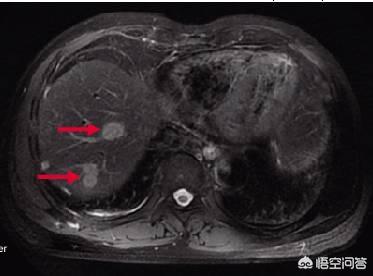

Lebermetastasen bei Dickdarmkrebs sind sehr häufig, und Dickdarmkrebspatienten müssen zunächst eine Bauch-CT und eine Brust-CT durchführen lassen, um festzustellen, ob es Leber- und Lungenmetastasen gibt. Durch die hämatogene Metastasierung folgt der Darmkrebs nicht nur der Lokalisation, sondern auch dem Blutkreislauf, die Krebszellen werden abgestoßen und gelangen über den Blutkreislauf in die Leber, wo sie Metastasen bilden, die eine sehr häufige Metastasierung von Darmkrebs darstellen. Sobald eine Lebermetastase auftritt, handelt es sich um ein fortgeschrittenes Stadium, und eine Lebermetastase ist nicht völlig unbehandelbar. Wenn es sich um oligometastatische Lebermetastasen handelt, die Zahl der Metastasen relativ gering und die Lage relativ gut ist, können sie durch eine gleichzeitige Resektion von Dickdarm und Leber beseitigt werden; wenn die Metastasen relativ groß sind, müssen sie durch eine systemische Chemotherapie bekämpft werden.

Die Inzidenz von Lebermetastasen bei Dickdarmkrebs ist hoch, etwa 50-70 Prozent, und einige werden nach der Operation oder vielleicht schon vorher entdeckt. Es ist nicht ungewöhnlich, dass kleine Primärherde und viele, große Metastasen auftreten.

Tumordurchmesser ist sehr klein, in der Regel 1-2mm, die Metastasen haben kann, wenn der Tumor ist sehr klein, ohne Lebermetastasen, mit TNM-Staging ist wahrscheinlich ein Stadium I Patienten, einfache Operation kann mehr als 90% der 5-Jahres-Überlebensrate, eine vollständige Heilung ist sehr wahrscheinlich, aber wenn Lebermetastasen auftritt, wird die Situation schlecht.